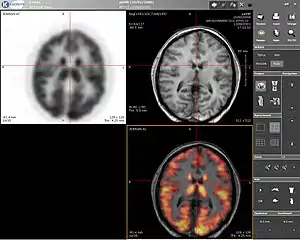

Computer screenshot showing a PET image (upper left), MRI image (upper right) and the combined PET-MRI image where PET data is overlaid over the MRI data (lower right)